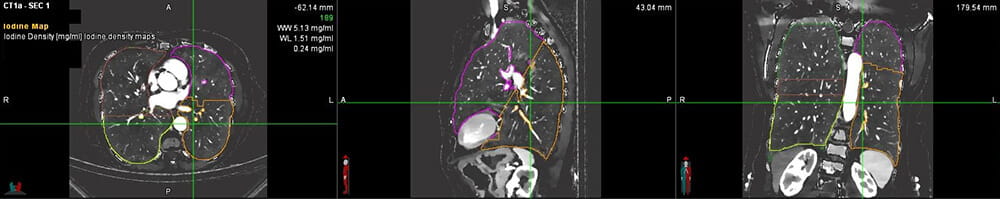

Dr. Avasarala received a CHEST Foundation grant to evaluate Dual Energy Computed Tomography (DECT) scans as an alternative to quantitative perfusion scans. He will be studying this with his co-investigator, Amit Gupta, MD, a DECT scanning expert in the Department of Radiology at University Hospitals Cleveland Medical Center. These DECT scans produce an iodine map that shows blood flow in the lungs.

“The main point of this project is to see how much blood flow changes in the lungs pre- and post-valve placement using dual-energy CT scans,” says Dr. Avasarala. “Every patient enrolled in the study will have a quantitative perfusion scan on file, as well. We want to explore the idea that patients may not need this scan prior to valve placement.”